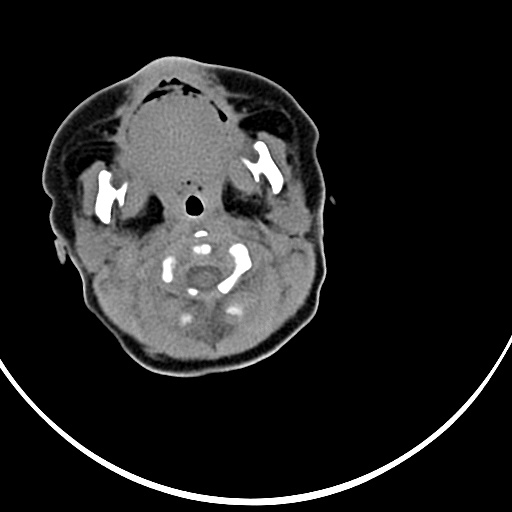

患者,男,1月,出生后一月,无明显诱因出现颈部左前方肿块。体检:左侧颈部轻度凸起包块,触之较硬。

患者,男,1月,左经部轻度凸起包块,质硬。

病灶与左侧胸锁乳突肌分界不清,软组织密度,不似囊性改变,从病人的年龄及病变性状首先要除外先天性斜颈(肌性斜颈)可能。

左侧胸锁乳突肌肿大,考虑产伤所致

胸锁乳突肌挛缩(斜颈)?